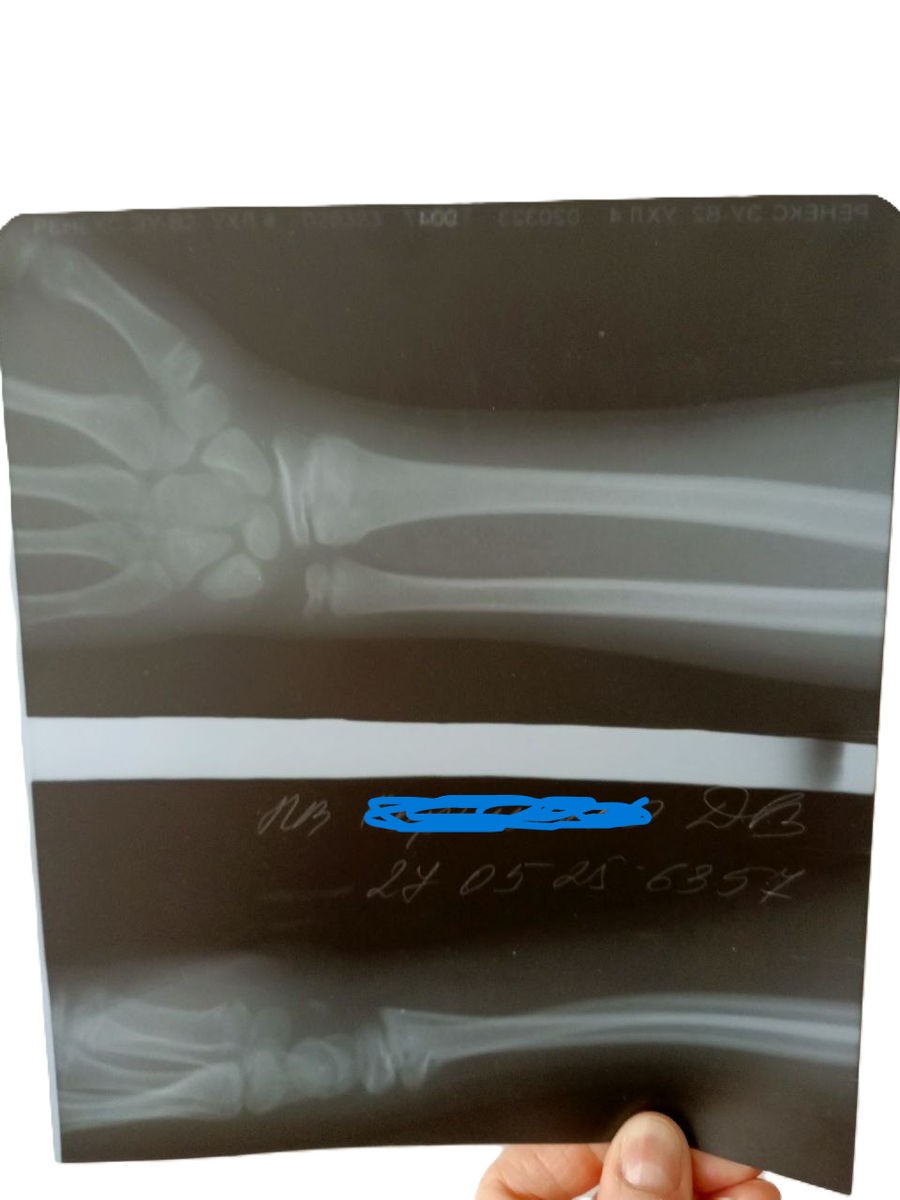

В травме нас оперативно зарегистрировали и отправили в общую очередь. Дело в том, что травмпункт при экстренных ситуациях у нас общий, находится в подвале городской взрослой поликлиники. Отсидели мы в общей очереди с дедушками, бабушками, детьми и взрослыми примерно час. Нас принял дежурный врач, тут же сделали снимок и наложили гипс. У сына оказался перелом запястья. Сказали, что перелом несложный, по типу зелёной ветки, достаточно походить в гипсе 2 недели.

Неделя прошла... Мы пришли на приём, врач посмотрел снимок и сказал, что в гипсе нам ходить месяц. Потому что в том месте, где перелом, находится точка роста и на неё очень большая нагрузка. Короче отправил нас гулять ещё 2 недели, дав направление на повторный рентген.

Ренген мы прошли (на удивление без очередей, врач принимала строго по времени), на следующий день забрали снимок, где было написано, что стояние костных отломков удовлетворительное, а значит гипс можно снимать.